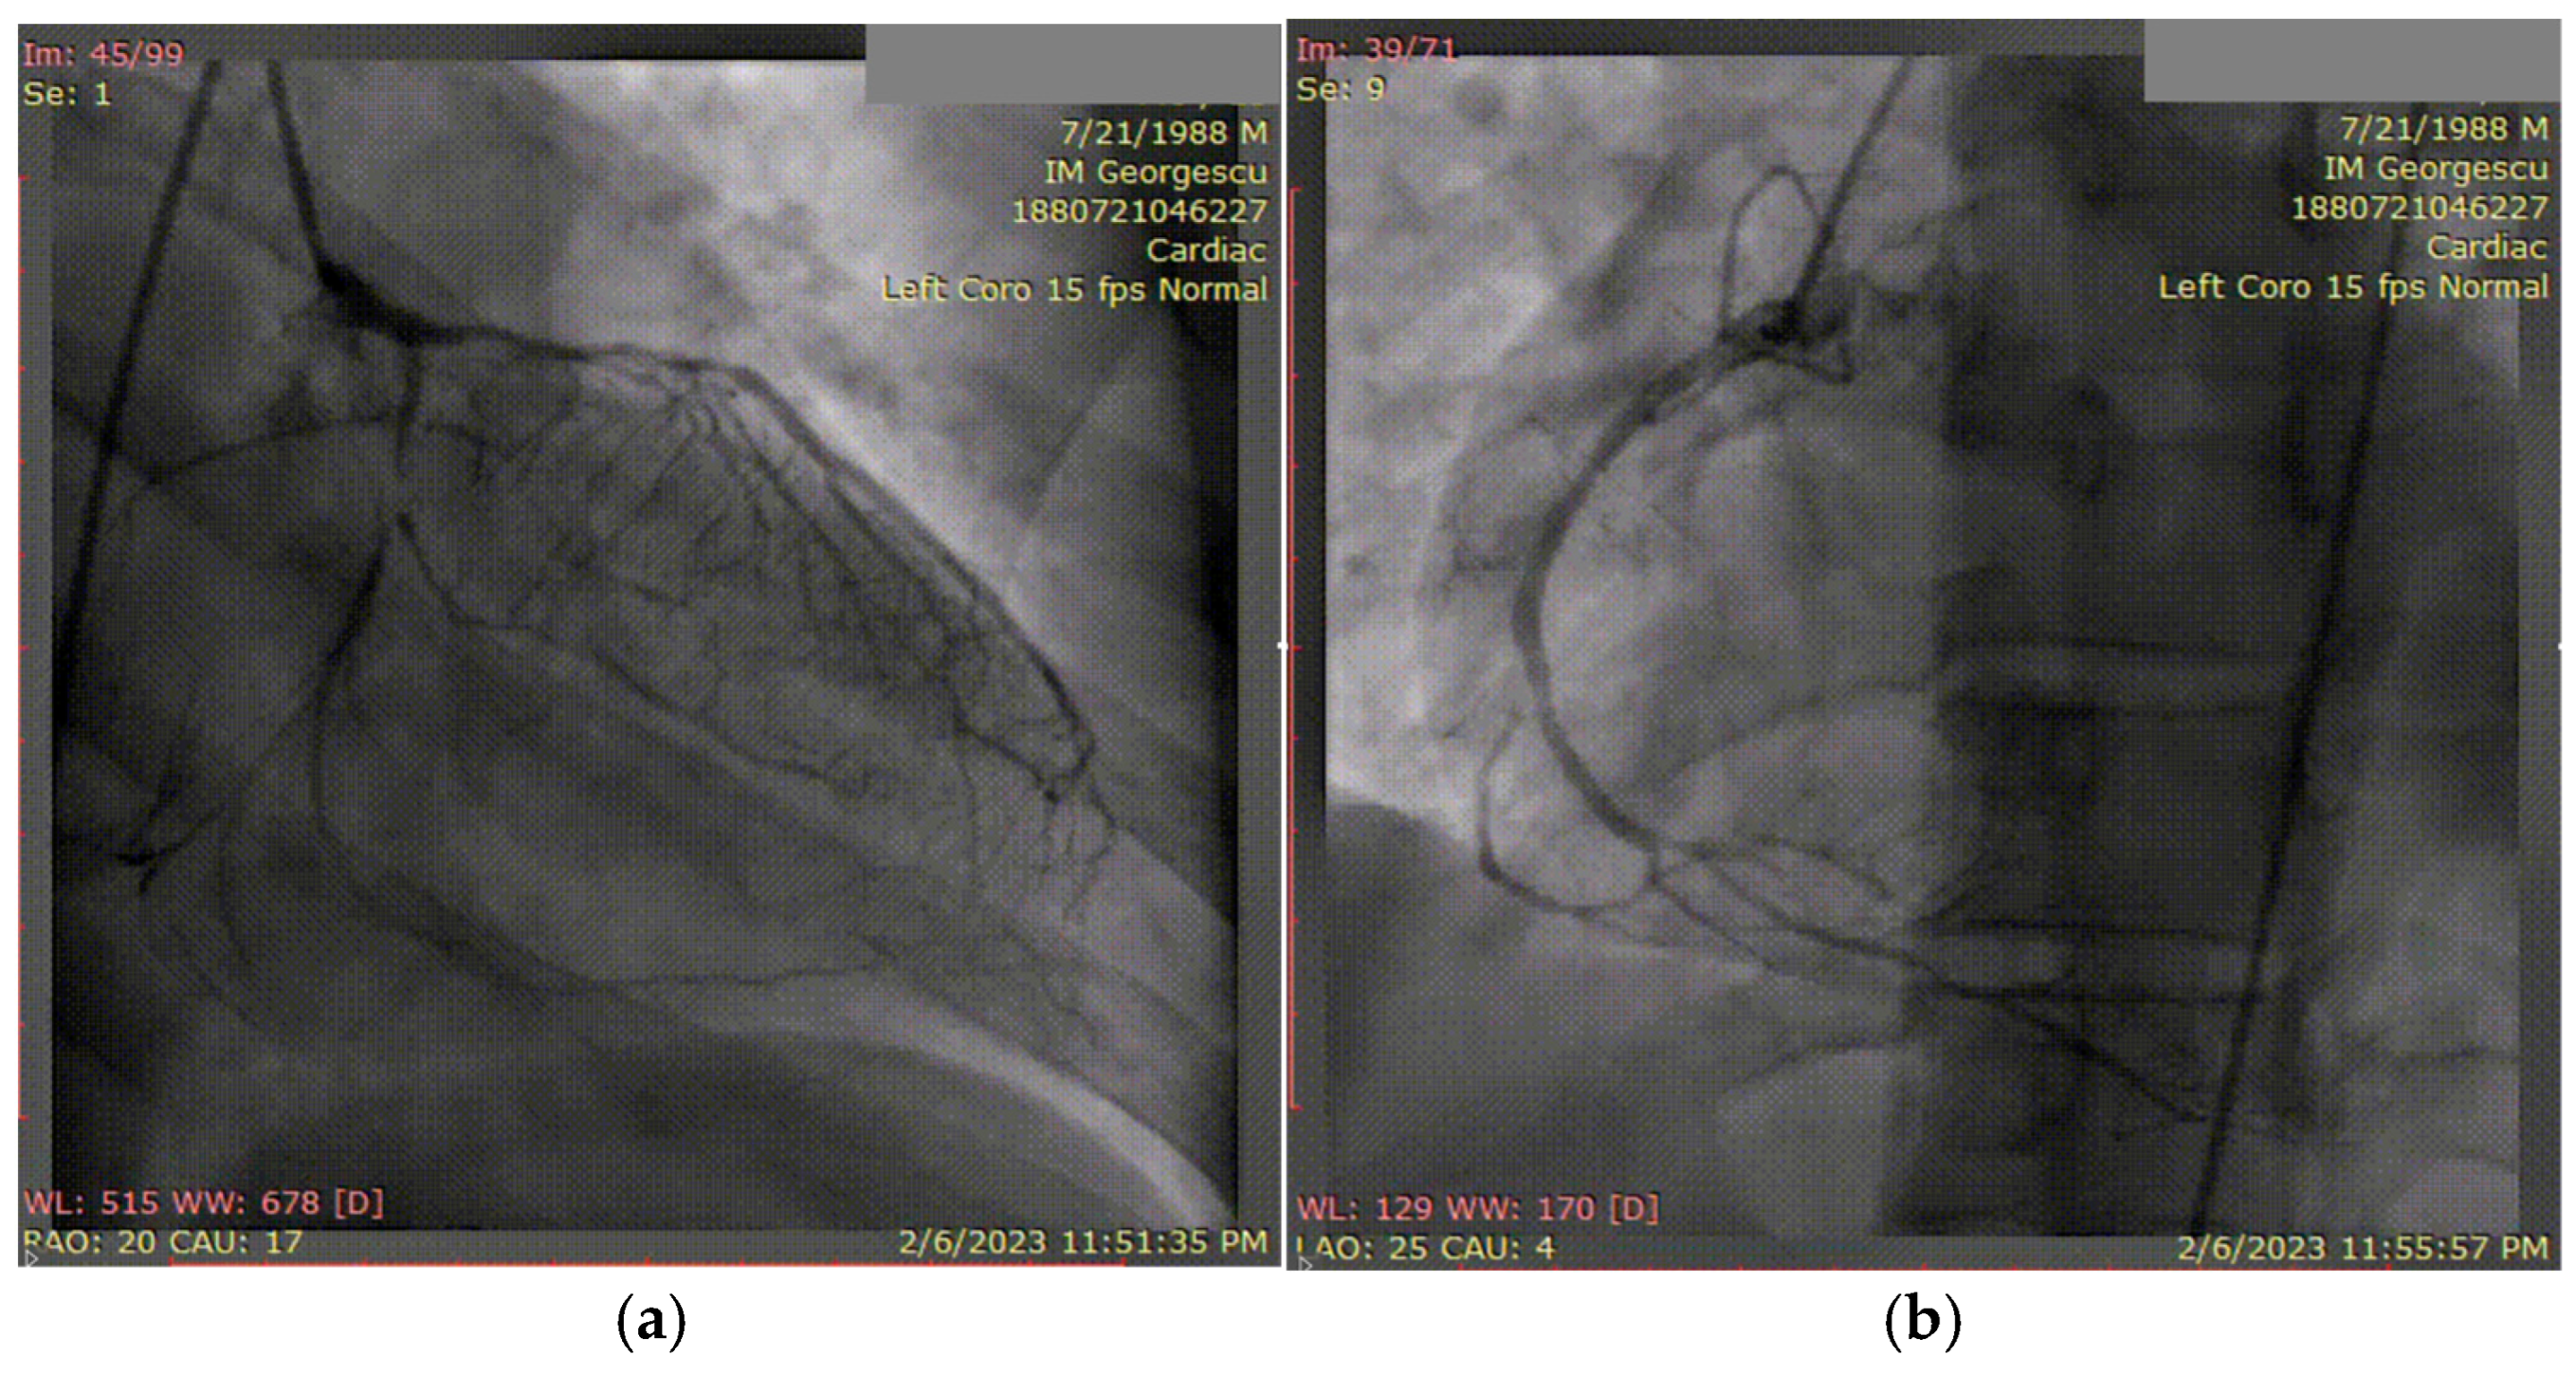

3.2. Case 2